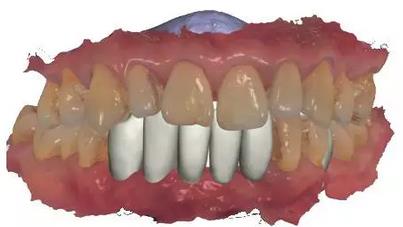

通過3Shape Dental System軟件同期設(shè)計(jì)臨時(shí)冠

手術(shù)導(dǎo)板數(shù)據(jù)發(fā)送至成都登特,通過BEGO打印機(jī)打印出導(dǎo)板,切削出臨時(shí)冠

臨時(shí)冠就位,即刻修復(fù),無咬合接觸

修復(fù)后全景片